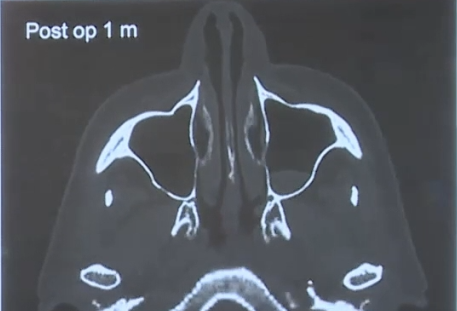

术后的核磁影像

这是术后一个月后,鼻子完好无损,唯一的变化是蝶窦现在是颅腔的一部分。